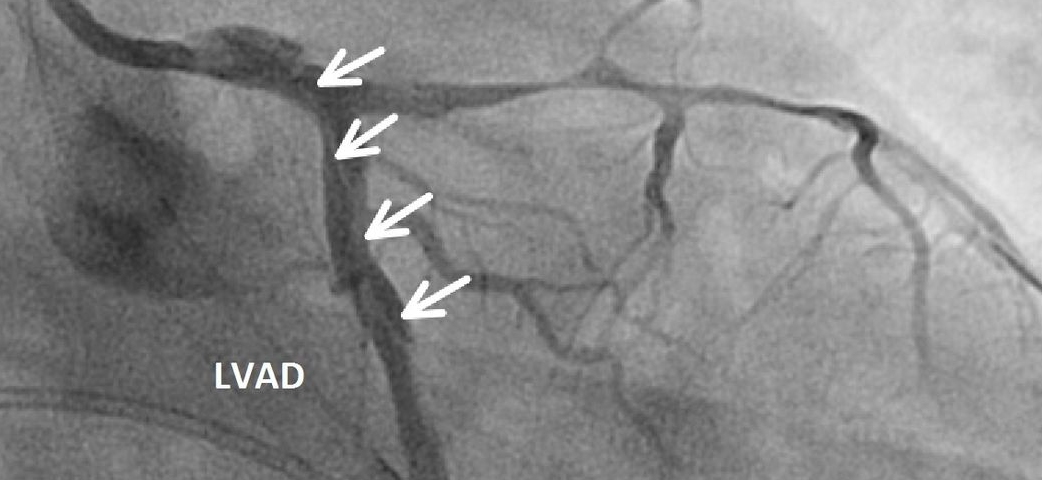

导管导致的严重冠脉夹层

严重冠脉夹层是指夹层导致真腔血流减少,并引起致命性心肌缺血。无论是由造影导管还是指引导管引起,严重医源性冠脉夹层多数都是导管头端造成夹层开始的。夹层可以沿圆周和纵向扩展并压迫真腔,导致冠脉血流减少,随后发生心肌缺血。当导管头端嵌顿时,注射造影剂会使夹层进一步延展。

当导丝已经送入远端真腔时,冠脉夹层并不会立即致命,因为术者可以通过导丝送入球囊扩张真腔,确保真腔血流。然而,如果导丝没有置于远端真腔,由于难以确保真腔血流,夹层的扩展可能是致命的。即使导丝已置于远端真腔,如果由于严重狭窄或钙化,术者无法送入球囊扩张真腔,冠脉夹层也可能是致命的。

3.2.2 IVUS指导[推荐]

当术者无法将导丝推送到假腔时,最佳选择是使用IVUS指导进行导丝操作。术者应通过植入在假腔中的导丝推送IVUS导管,并识别假腔的起点。然后,术者应确认在假腔起点处残余真腔的位置。术者可以利用侧支方向、IVUS导管在近端真腔和指引导管内的位置以及导丝和IVUS导管的相对位置等信息,在透视下识别残余真腔的位置和方向。然后,术者就能在 IVUS指导下进行高效的导丝操作,以快速进入真腔。尽管OCT指导下的 PCI近年来有所增加,但在夹层情况下OCT是禁忌的。OCT成像需要冲洗清除血液,这会导致假腔扩大。即使OCT器械已经置于手术台上,在严重冠脉夹层时也应准备IVUS导管。